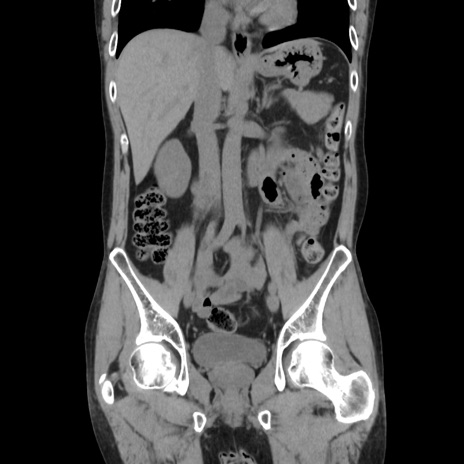

症例37(冠状断像)

【症例】40歳代 男性

【主訴】腹痛

【現病歴】4時間ほど前に電車に乗車中に臍部上より腹痛出現。徐々に増悪し起立困難となり、救急外来受診。生ものは数日食べていない。今朝お雑煮を食べた。

【身体所見】BT 36.8℃、BP 117/84mmHg、HR 91/min、SpO2 97%、苦悶様、腹部:臍上部広範囲圧痛あり、反跳痛±

【データ】WBC 8100、CRP 0.03

横断像